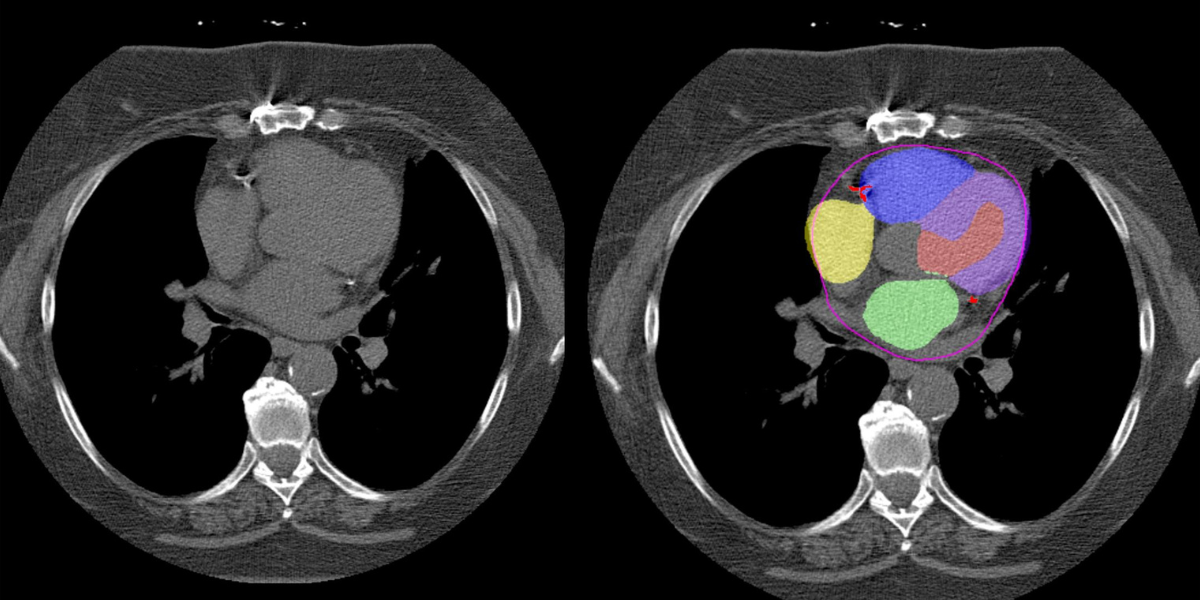

The researchers combined two previously validated algorithms:one developed by Slomka and colleagues that measures CAC, and other that can segment cardiac chamber volumes, to analyze routine chest CT scans (i.e., low-dose scans without contrast and gating). They evaluated scans from 24,354 patients who underwent CT as part of the National Lung Screening Trial and identified several cardiac factors that were associated with an increased risk of death, such as a large number of CACs and increased mass or volume of specific cardiac chambers. What’s more, the researchers found that the combination of all factors (including clinical data such as age and medical history) was a better predictor of death than any factor alone.

Beyond the CAC, the shape and size of the different chambers of the heart can also help predict heart disease. For example, having an enlarged left atrium. has been shown be a predictor of heart failure. But estimating myocardial mass and the volume of each chamber of the heart typically requires the use of a contrast agent, which is not used in all routine chest CT scans.